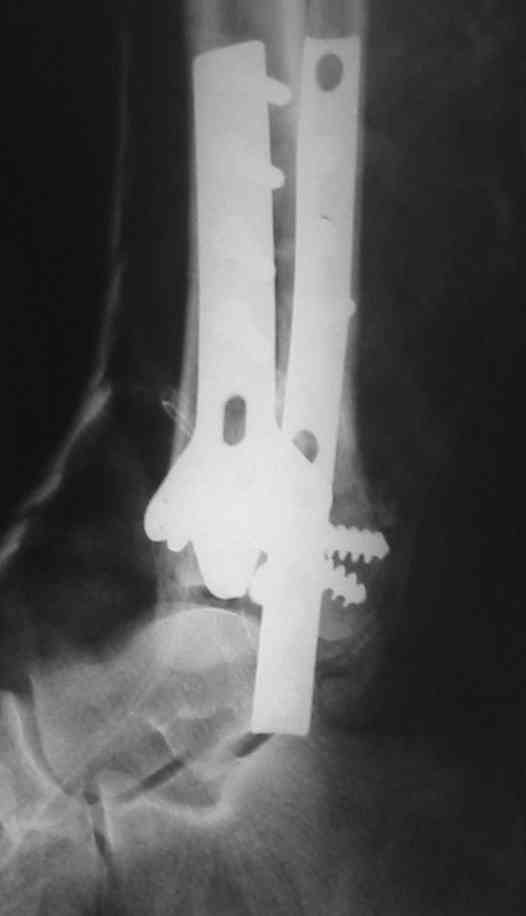

Посмотрим вроде прошло если понравится напишите расскажу как это сделать.По принципам АО кстати при поступлении сначала восстанавливают длину малоберцовой кости фиксируют пластиной 1/3 трубки потом накладывают аппарат наружной фиксации и через 7-10 дней открыто восстанавливают большеберцовую кость.С уважением Дрягин

На рентгенограммах типичный перелом пилона по типу С-3. есть опыт до 100 открытых опреаций у нас в клинике. 20 примерно в год. Принцип один -все внутрисуставные переломы нуждаются в открытой репозиции и внутренней стабильной фиксации. При поступлении КТ не надо, так как получается только нагромождение костей. Истинной картины нет. Главное восстановить длину малоберцовой кости - это ключ к успеху. При поступлении меньше всего надо думать о сосудистых расстройствах, т.к. сама операция и репозиция даже сначала частичная даёт улучшение сосудитых нарушений. Причём очень быстро. Операция в 2этапа. При поступлении доступ позади наружной лодыжки, причём обязательно. После этого репозиция малоберцовой кости и фиксация пластиной 1/3 трубки под винт 3,5. Дренаж и любой аппарат наружной фиксации. Затем после спадения отёка на 5-7-10 день аппрат снимается и дугообразный разрез спереди от медиальной лодыжки 10-12 см. Главной чтобы расстояние между 1 и вторым разрезом было не меньше 7-8 см. Тогда не будет некрозов лоскутов. Таранная кость используется как матрица на неё укладываются отломки и фиксируются пицами. Ренг-контроль. Отломки лежат все отдельно, но ничего не высыпется. При переломах С-3 всегда нужна костная пластика (из крыла). Фиксация пластиной лист клевера простой или LCP. Гипс не нужен. Дренаж до 48 часов. Операция длится 3-4 часа обязательно без жгута. Посылаю примерно такой же случай.